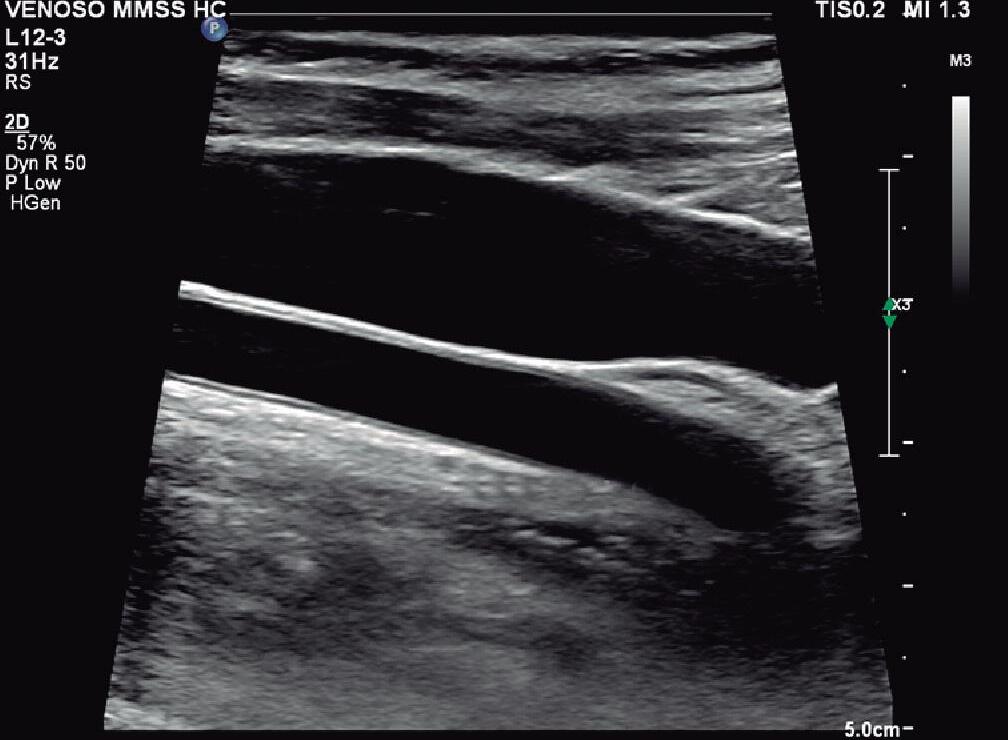

Para o estudo das veias centrais, o método de escolha é a ultrassonografia (USG) vascular, por ser não invasiva, não ter radiação ionizante e não utilizar contraste.1

Na avaliação das veias centrais pré-implante de cateter, deve-se estudar toda a extensão possível da veia jugular interna (VJI) (Figuras 5.1 a 5.3) e da veia subclávia (VSC) (Figuras 5.4 a 5.6), locais mais comuns de implante de cateter venoso central (CVC). Esse estudo é fundamental, já que a prevalência de estenose central pode variar de 9% a 51% nos pacientes em hemodiálise.2 Além disso, o aumento do número de procedimentos nessas veias, por exemplo, para a colocação de cateter central de inserção periférica (PICC; do inglês, peripherally inserted

central catheter) e implante de marcapasso, torna o estudo por USG vascular imprescindível para o médico que atua nessa área.

A USG vascular deve buscar identificar trombose venosa recente ou, principalmente, trombose venosa antiga decorrente de procedimentos prévios, o que seria uma contraindicação para nova intervenção naquele segmento.

Além da VJI e da VSC, já citadas, o estudo por USG vascular das veias centrais deve incluir, sempre que possível, a identificação das veias braquiocefálicas direita e esquerda (Figuras 5.7 e 5.8). Para isso, o paciente é colocado em posição supina com os braços levemente abduzidos e a região cervical exposta.1 O estudo deve ser realizado sempre bilateralmente, considerando-se que pode haver até 24% de estenose central contralateral ao implante do cateter.2

A VJI e a VSC são insonadas diretamente utilizando -se a escala de cinza (modo B) e o Doppler colorido. O transdutor usado é do tipo linear de frequência entre 3 e 12MHz.3 O modo B, ou escala de cinza, é a etapa inicial do exame e deve mostrar um lúmen anecoico. A compressão

da veia com o transdutor indica a ausência de trombos. As medidas de velocidade devem ser obtidas com a veia no plano longitudinal e o ângulo de insonação sempre menor ou igual a 60° e paralelo ao fluxo do lúmen venoso. O volume de amostra deve ser pequeno e colocado na área